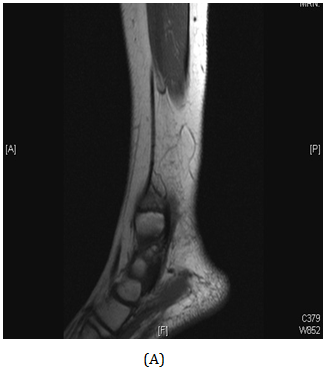

A girl, 11yearsold Saudi presented to us with progressive swelling of the left lower limb, localized above the left ankle with complaints of pain and limping gait. She had visited many clinics for her pain and swelling with no relief to her symptoms. The patient was examined clinically and there was a swelling in the lateral aspect of the distal leg tender firm too hard with intact skin over it, 4x3 cm, no other systemic clinical finding of note. X-ray of the left leg (Figure 1) showed aggressive lytic lesion of the distal fibula. Thence patient was investigated with basic lab works plus systemic and local staging for further diagnosis. She was admitted under us in pediatric surgical ward for open biopsy of the distal fibular lesion and CT of the lower limb (Figure 2) showed destructive bone lesion involving the distal end of the fibula associated with extensive destruction and aggressive periosteal reaction associated with large soft tissue mass 4.5 x 5 cm in maximum axial dimension. Also, MRI of the lower limb (Figure 3) showed there is a large destructive bone lesion involving the distal diaphysis of the left fibula. This lesion does not cross the growth plate. It is associated with aggressive periosteal reaction along with a large soft tissue mass that appears of high signal intensity in T2 and intermediate to low signal intensity in T1 sequences. This was followed by technetium-99m MDP scintigraphy (Figure 4), it showed an increased tracer uptake in the distal left fibula, extending to the left ankle and the left foot. Excisional biopsy was taken from the proximal and distal margin of the lesion in the left fibula which confirmed Ewing's Sarcoma. According to the histopathology department, they reported that there is no evidence of residual tumor i.e free resection margins. (Figure 5) The patient was referred from us to pediatric oncology clinic for further evaluation. She was electively admitted to the hospital for staging and central line insertion to start chemotherapy. She treated as per Ewing sarcoma protocol in our hospital. Patient was put on neoadjuvant chemotherapy which included vincristine, cyclophosphamide, doxorubicin and etoposide, and if osfamide 3 times weekly. After 6 months of chemotherapy, we recommend to her family to do a surgery. We did a wide surgical resection of the tumor in the left leg. Subcutaneous tissue was dissected and isolation of superficial peroneal nerve was done. Dissection of lateral compartment of the left leg up to 16cm proximal to the lateral malleolus and distally, until the distal physis (Figure 6). The tendons of the peroneus longus, peroneus brevis, and flexor halluces longus were sacrificed and the ruminants were used to reconstruct for the lateral aspect of the left ankle using suture anchors (Figure 7). K-wires were used to do temporary arthrodesis (Figure 8). The surgical wound was closed in layers. VAC dressing was also applied as standard care management in Oncology cases at KFMC and backs lab was applied (Figure 9). The last MRI done for the patient showed there is altered signal intensity of the soft tissue with post-contrast enhancement. However, the dimensions of this area of altered signal intensity are decreased as compared to previous MRI. There is no evidence of soft tissue mass lesion (Figure 10). According to the last patient's follow up after six months post-operation it shows no Valgus deviation, normal ankle motion, mobilizing full weight bearing with splint assistant during physical examination (Figure 11). Also, X-rays and MRI finding shows no residual mass lesion or local recurrence.

Figure 3 MRI of the lower limb showed aggressive bone lesion involving the distal diaphysis of the left fibula associated with huge soft tissue tumor.